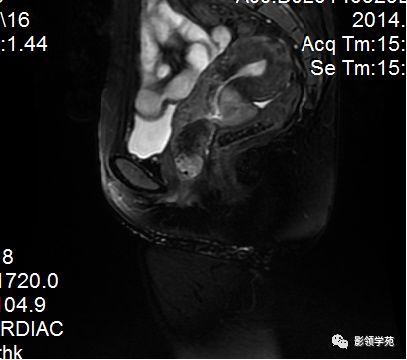

- 扫描序列:SAG T2WI,AXI T1WI+T2WI, COR T2WI 。其中SAG T2WI最重要

- 呈前倾前屈位

- 屈:宫体与宫颈间夹角为170度

- 倾:宫体与阴道间夹角为90度

- 前面借膀胱阴道隔与膀胱底相邻;后面借直肠子宫陷凹及直肠阴道隔与直肠相邻